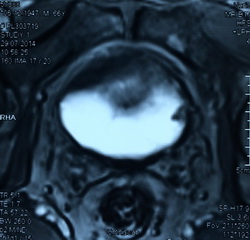

Из анамнеза: в июле 2014 года после физической нагрузки отметил появление крови в моче с бесформенными сгустками. В поликлинике по месту жительства при ультразвуковом исследовании выявлена аденома предстательной железы. Консультирован в клинике урологии УКБ№2 Первого МГМУ им. И.М. Сеченова, при УЗИ заподозрена опухоль мочевого пузыря. Выполнена МРТ органов малого таза, по данным которой по левой боковой стенке мочевого пузыря определяется экзофитное образование размерами 0,9х0,8х0,7мм. Также выявлена аденома предстательной железы. Госпитализирован в плановом порядке для оперативного лечения

Рис№1. УЗИ мочевого пузыря и предстательной железы.